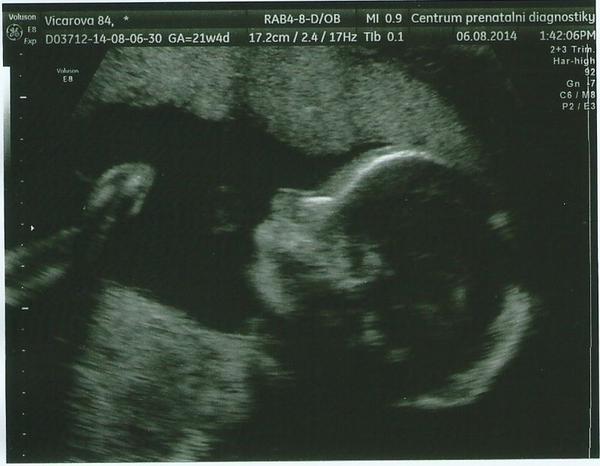

@dorabell děkuji moc ke gratulaci 🙂 bylo to překvapení veliké (na začátku tipovali chlapečka) - ale jsme přešťastní, že je ta naše princezna v pořádku a má se čile k světu (váží 450g a měří 25 cm - takže velká slečna) 😀 A u tebe se také nebojím, dopadne to dobře a tvůj mrňousek už to s tebou určitě tentokrát dotáhne do krásného porodu 🙂 Ale do včerejška mě také svíral neustálý strach - ale paní doktorka byla naprosto úžasná, poměřila a zkontrolovala snad úplně všechno co šlo a tak nádherně nám vše vysvětlila, že se můj muž nakonec i rozhodl změnit názor na 3D ultrazvuk (nechtěl ho) a půjdeme na něj - jen si vyžádáme tuhle a jedině tuhle lékařku 😀